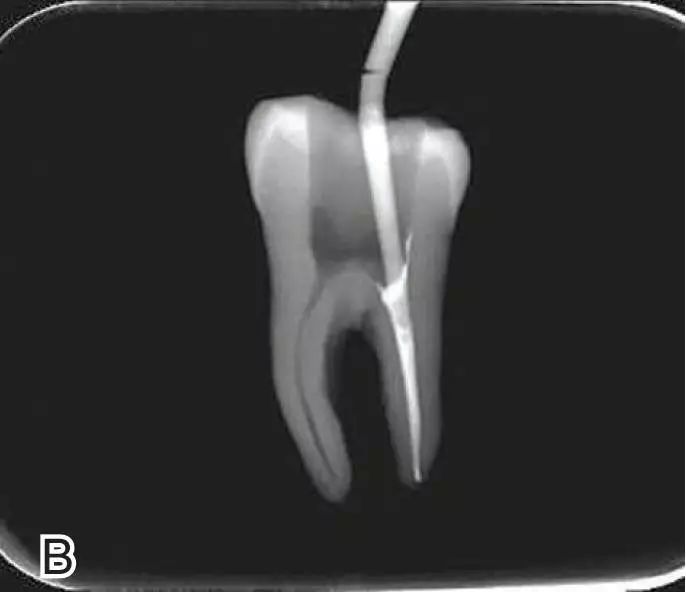

试尖

选择非标准牙胶尖(如0.04、0.06 锥度牙胶尖)作为主尖,型号一般与根管预备最大号的器械型号一致,能到达距根尖0.5~1 mm 处,主尖尖段与根管壁紧密接触。拍试尖X 线片进行确认。